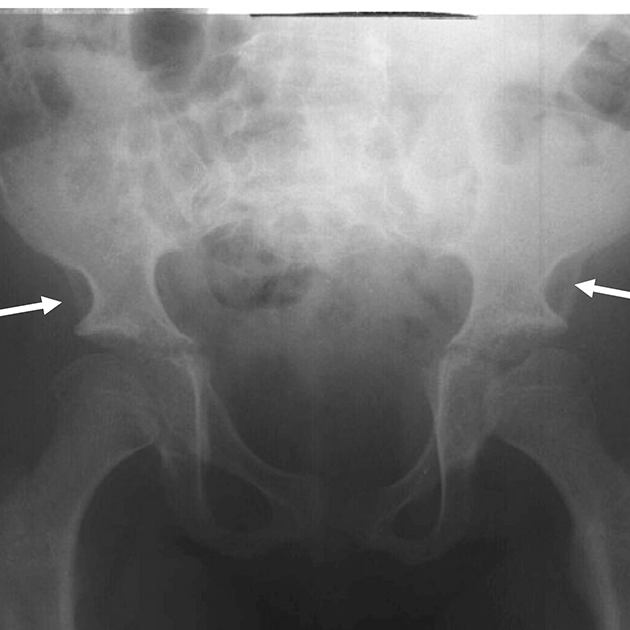

Radiografía donde se observan manifestaciones de disostosis múltiple en la pelvis y cadera de un paciente con MPS. Crestas ilíacas redondeadas, paredes laterales ilíacas de doble contorno (flechas), y cuellos femorales elongados.

Reproducido con permiso de Lachman, J Pediatr Rehabil Med, 2010.

Radiografía de pelvis y cadera anteroposterior en un paciente de 27 años con Morquio A, donde se muestra epífisis femoral capital levemente displásica con estrechamiento del espacio articular y esclerosis (artrosis degenerativa).

Fuente: Skeletal Radiology, volume 43, issue 3. Lachman RS, Burton BK, Clarke LA, Hoffinger S, Ikegawa S, Jin D-K, Kano H, Kim O-H, Lampe C, Mendelsohn NJ, Shediac R, Tanpaiboon P, White KK. Mucopolysaccharidosis IVA (Morquio A syndrome) and VI (Maroteaux-Lamy syndrome): under-recognized and challenging to diagnose. Pages 359-369. Copyright (C) Lachman RS, Burton BK, Clarke LA, Hoffinger S, Ikegawa S, Jin D-K, Kano H, Kim O-H, Lampe C, Mendelsohn NJ, Shediac R, Tanpaiboon P, White KK 2014.